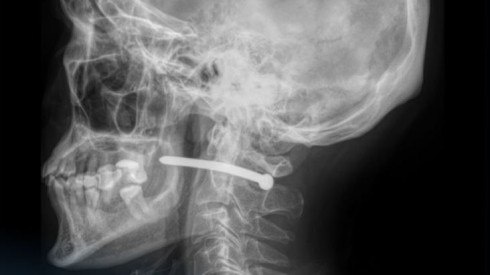

В Петропавловске мужчина едва не погиб во время ремонта: он случайно выстрелил себе в шею гвоздём из пневмопистолета, передаёт корреспондент Tengrinews.kz.